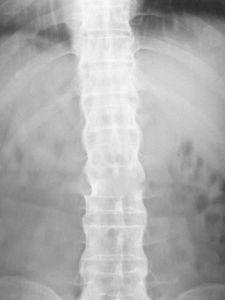

脊柱受損圖片 強直性脊柱炎屬於脊柱關節綜合症,主要影響腰椎、胸椎以及骶髂關節,現在相信與免疫失調及遺傳因子有關。除此以外,強直性脊柱炎尚能引發眼虹膜炎症以及影響到身體之其他器官。

對AS的診斷有極為重要的意義,98%~100%病例早期即有骶髂關節的X線改變,是本病診斷的重要依據。早期X線表現為骶髂關節炎,病變一般在骶髂關節的中下部開始,為兩側性。開始多侵犯髂骨側,進而侵犯骶骨側。可見斑點狀或塊狀,髂骨側明顯。繼而可侵犯整個關節,邊緣呈鋸齒狀,軟骨下有骨硬化,骨質增生,關節間隙變窄。最後關節 間隙消失,發生骨性強直。骶髂關節炎X線診斷標準分為5期:0級為正常骶髂關節,Ⅰ期為可疑骶髂關節炎,Ⅱ期為骶髂關節邊緣模糊,略有硬化和微小侵襲病變,關節間隙無改變,Ⅲ期為中度或進展性骶髂關節炎,伴有一項(或以上)變化:近關節區硬化、關節間隙變窄/增寬、骨質破壞或部分強直,Ⅳ期為關節完全融合或強直伴或不伴硬化。

脊柱病變的X線表現,早期為普遍性骨質疏鬆,椎小關節及椎體骨小梁模糊(脫鈣),椎體呈“方形椎”,腰椎的正常前弧度消失而變直,可引起一個或多個椎體壓縮性骨折。病變發展至胸椎和頸椎椎間小關節,間盤間隙發生鈣化,纖維環和前縱韌帶鈣化、骨化、韌帶骨贅形成,使相鄰椎體連合,形成椎體間骨橋,呈最有特徵的“竹節樣脊柱”。原發性AS和繼發於炎性腸病、Reiter綜合徵、牛皮癬關節炎等伴發的脊柱炎,X線表現類似,但後者為非對稱性強直。在韌帶、肌腱、滑囊附著處可出現骨質糜爛和骨膜炎,最多見於跟骨、坐骨結節、髂骨嵴等。其他周圍關節亦可發生類似的X線變化。

竹節樣脊柱改變 在於控制炎症,減輕或緩解症狀,維持正常姿勢和最佳功能位置,防止畸形。要達到上述目的,關鍵在於早期診斷早期治療,採取綜合措施進行治療,包括教育病人和家屬、體療、理療、藥物和外科治療等。